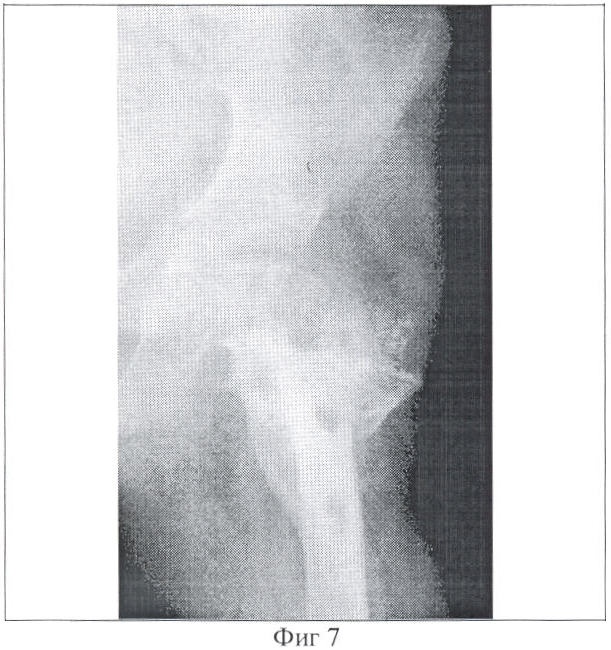

Фиг. 7 – копия рентгенограммы пациента через один месяц после снятия аппарата;

В послеоперационном периоде в течение двух месяцев осуществляли поддерживающую компрессию в зоне остеотомии 1,5 мм один раз в неделю. Через два месяца больной повторно взят в операционную. Под эндотрахеальным наркозом произведена остеотомия на границе средней и нижней трети бедра, через зону которой интромедуллярно проведены две спицы с остеоиндуцирующим покрытием. В послеоперационном периоде с 6 дня начата дистракция 1 мм в сутки между опорами, установленными на дистальном метафизе и на границе верхней и средней трети бедра. (Фиг. 5). Продолжительность дистракции составила 50 дней. Через две недели после окончания дистракции удалены сквозные спицы, проведенные в проксимальном отделе бедра, опора, установленная в вертельной области, демонтирована (Фиг. 6). Продолжительность фиксации в зоне межвертельных остеотомий составила 126 дней Продолжительность фиксации чрескостным устройством дистракционного регенерата – 75 дней. Интрамедуллярные спицы удалены через месяц после демонтажа чрескостного устройства. На контрольной рентгенограмме отмечается полная консолидация в местах выполненных остеотомий, частичная оссификация шейки бедренной кости (Фиг. 7). Проведен курс реабилитационного лечения.